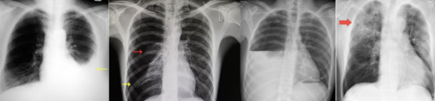

1. A 37-year-old man, with no known medical illness, came for a routine medical check-up. His chest radiograph is presented to you. Identify the incorrect statement with respect to the X-ray shown below.

1. The structure marked as number 2 is right ventricular border

2. The structure marked as 1 is the trachea

3. The structure marked as 3 is the left ventricular border

4. The structure marked as 4 is the aortic arch